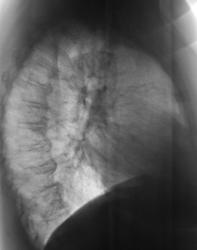

После расшифровки цифровых флюорограмм, пациент взят на контроль, дообследован. Ваше мнение уважаемые коллеги?

Можно предположить гиповентиляцию S2. Необходима КТ.

А если нет возможности сделать КТ, выполнить линейную томографию на в/долевой и сегментарные бронхи в/доли справа, бронхоскопию... В связи с этим у меня вопрос: Валентин Львович, я знаю у вас очень много случаев туберкулеза, но почему ваши лаборанты практически никогда не делают сразу срезы на бронхиальное дерево?

А где предыдущие данные, или это "с хутора"? Тогда КТ надо или бронхоскопию, если терять нечего - динамика покажет.

Вот посему, мы и предположили, наличие, как ранее называли, перибронхиального рака. Правда сейчас, он по всей видимости, отнесен к одному из видов БАР.

а по каким признакам здесь заподозрен БАР? Я почему то был уверен что это туберкулёз?

Туберкулез, в данном случае, нельзя исключить из дифряда, но он явно не первый.